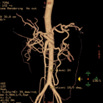

Abd Aorta MIP

显示腹部主动脉及其主要分支血管的起源、走形及其它的形态